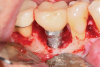

After local anesthesia was administered, full-thickness flaps were elevated from the buccal and lingual aspects of tooth No. 27 to the distobuccal and lingual aspects of tooth No. 31. Removal of granulomatous tissue from the implant site allowed visualization of a combination lesion with two walls at the distal and two to three walls at the mesial with a circumferential configuration on the lingual (Figure 12). The surface was initially treated with a 50% solution of citric acid for 30 seconds, which was burnished on with cotton pellets followed by thorough rinsing with sterile saline. This was followed by implantoplasty using 12-fluted followed by 30-fluted surgical-length finishing burs that provided access to the base of the defect. Because the crown was cemented, which obviated access, a matte-like surface could not be achieved; thus, the goal was to reduce the threads and remove the outer affected surface to expose fresh titanium (Figure 13). At this stage, the implant was wiped again with citric acid and rinsed with sterile saline.

Fig 12. The lesion was visualized upon flap reflection. A three- to two-wall lesion on the mesial wrapped to the lingual, while the distal had a two-wall lesion that also extended to the lingual as a moat.

Figure 12

Fig 13. Implantoplasty was completed. Some bleeding at the distal obscured one thread that was impossible to plasty. The surface was subsequently wiped with citric acid prior to grafting.

Figure 13